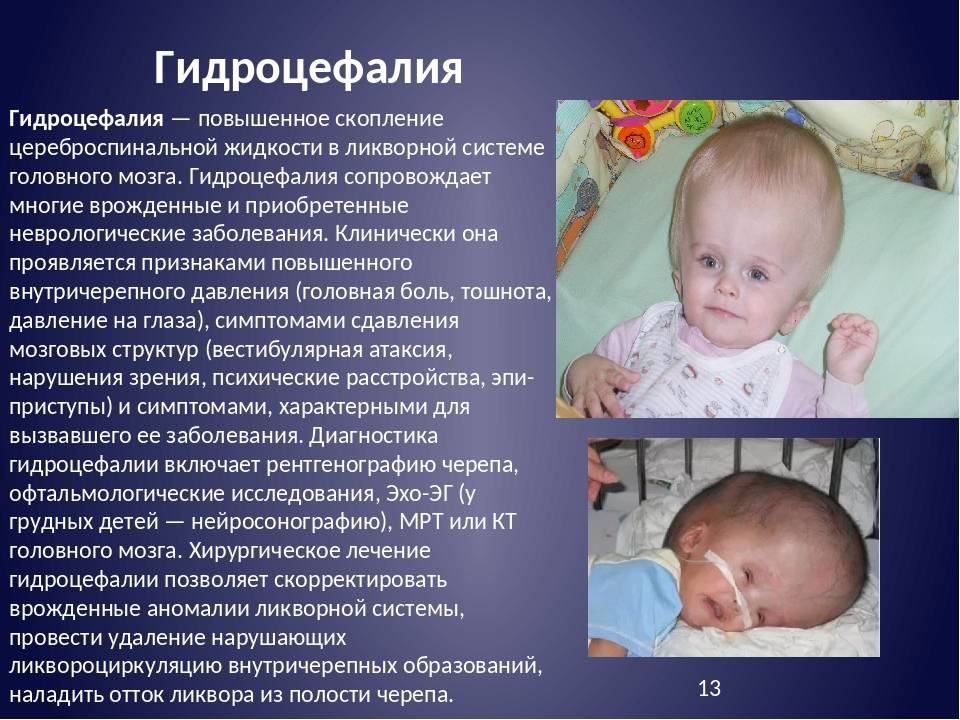

Признаки умеренно выраженной наружная

Признаки умеренно выраженной наружная 113 фото